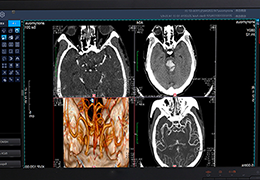

View X-Ray CT & MRI Scans Fast and Easily

FREE and easy to use 3D DICOM Viewer – for surgeons and patient education

Designed for surgeons, Pro Surgical 3D makes it easy to view patient scans quickly. Pro Surgical 3D facilitates the optimal 3D treatment and assessment workflows based on X-ray CT and MRI scans – and best of all, it’s FREE!

High-quality and fast 3D reconstruction and 3D rendering

Performs 3D reconstruction and volume rendering.

Multi-planar slicing.

Oblique slicing.

Side-by-side comparative assessment for pre- and post-operative scans.